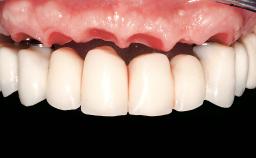

Immediate Loading of Eight Implants in the Maxilla and Six Implants in the Mandible and Final Restoration with Three-Unit and Four-Unit FDPs

Prosthesis Type FDP

Defining Characteristics Fully edentulous upper jaw to be rehabilitated with an implant-borne fixed dental prosthesis